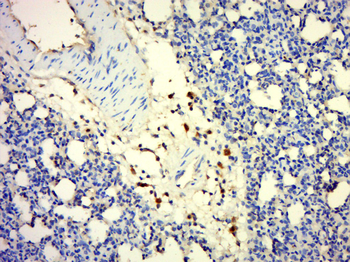

IQCF5 Rabbit Polyclonal Antibody

IF, IHC-Fr, IHC-P

应用稀释比例:IHC-P=1:100-500, IHC-F=1:100-500, IF=1:100-500